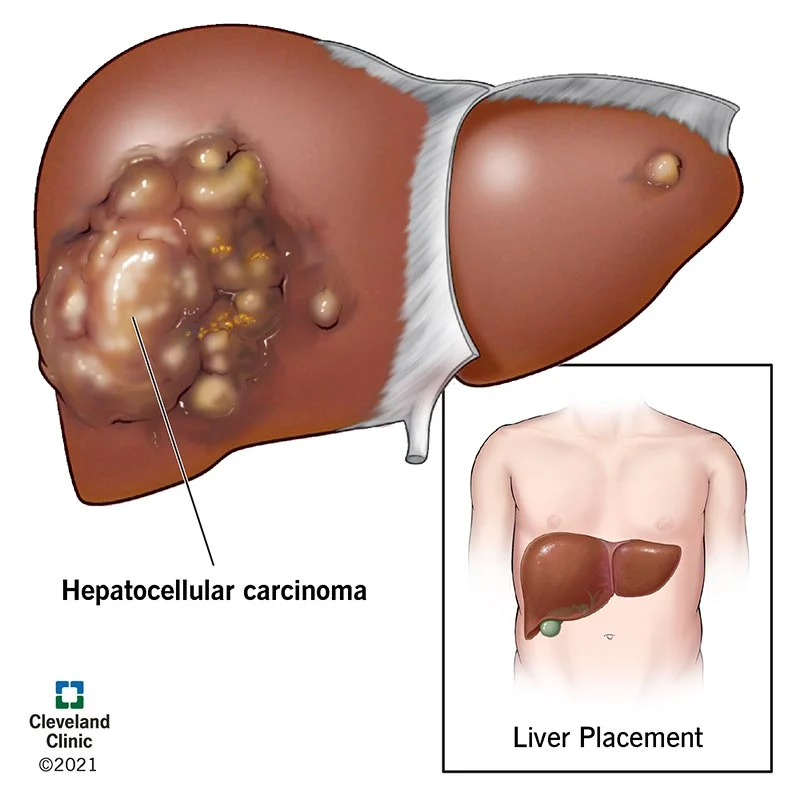

Tumors are abnormal masses of tissue that form when cells begin to reproduce at an increased rate. Both noncancerous (benign) and cancerous (malignant) tumors can develop in the liver.